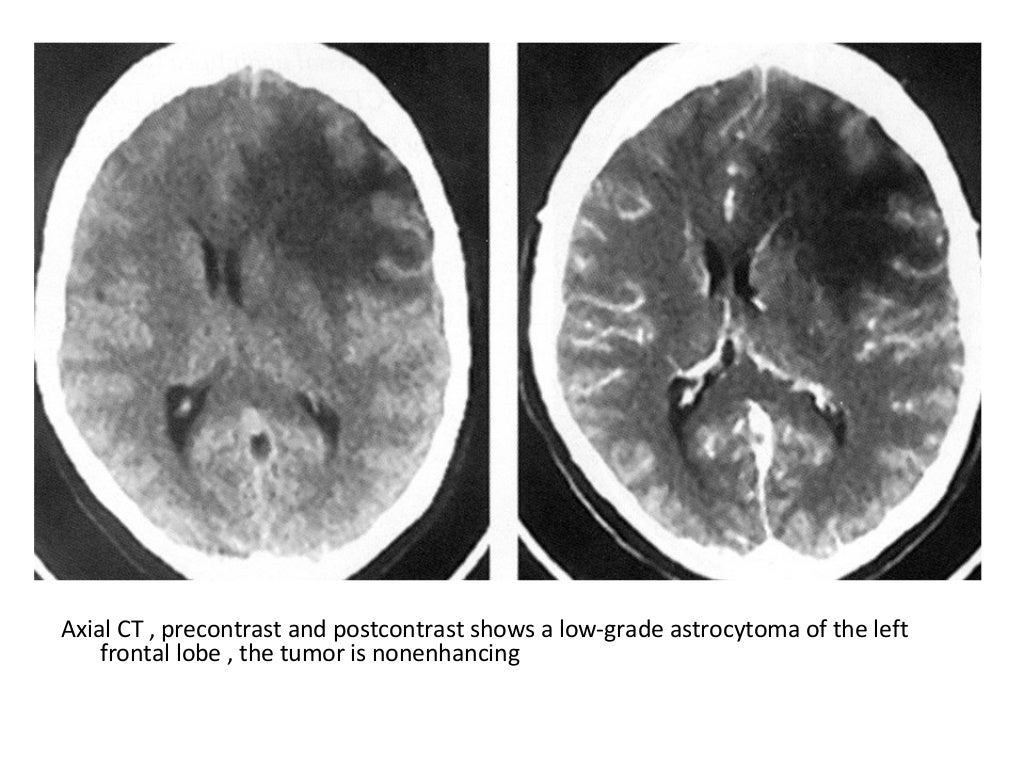

MRI Distinguishes Brain Lesions | Diagnostic Imaging

MRI Distinguishes Brain Lesions | Diagnostic Imaging from cdn.sanity.io